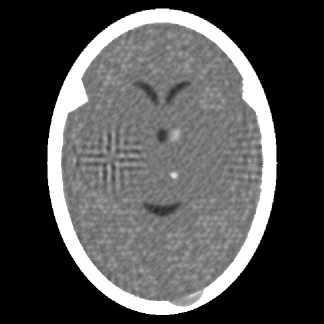

The PSM was implemented as described in Subsection 5.2.1. In particular, it started with the zero vector, for which . It was stopped according to the Stopping Rule (P3), the iteration number at that time was 815 and the value of the proximity function was , which is very much smaller than the value at the initial point. The computer time required was 2217 seconds. The TV of the output was 919, which is less than that of the phantom, indicating that the PSM is performing its task of producing a constraints-compatible output with a low TV. This output is shown in Figure 2(a).

As summarized in Table 1, with the stopping rule that guarantees that the output of the SM is at least as constraints-compatible as the output of the PSM, the SM showed superior efficacy compared to the PSM: it obtained a result with a lower TV value at less than one twentieth of the computational cost.